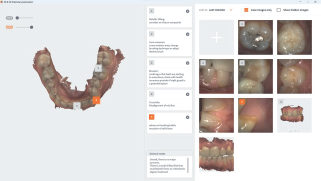

OVO brings you to the heart of patient communication. Equipped with a Tablet and 3DISC Scan&Tell, the dentist can show and explain options to the patient to increase treatment acceptance rate. 3DISC Scan&Tell 2D images and 3D scans make it easier to discuss treatment possibilities with the patient.

Preliminary Exam

The ultimate discuss & show tool, to enhance dentist-patient dialogue and promote patient confidence.

Live View Screenshot

The Live View Screenshot tool enables you to take screenshots during the scanning process, to be included in the Case Review and final Export, allowing you to pinpoint problem areas and monitor treatment progress. It also provides valuable information to technicians on tooth texture, margin definitions, etc..